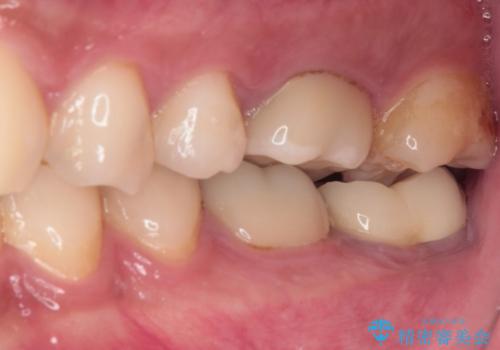

- 間もなく海外赴任という状況で奥歯のクラウンが割れてしまったとのことで来院された患者様です。

下顎の1番奥の歯であり、歯肉に覆われている部分が大きいためセラミックの十分な厚みが取れない状態でした。

強化セラミックを用いたオールセラミッククラウンにて補綴治療を行うこととしました。

十分な土台の高さを確保できない状態であったので、維持力のある土台の形態に整えることで、極力長持ちする治療を心がけました。